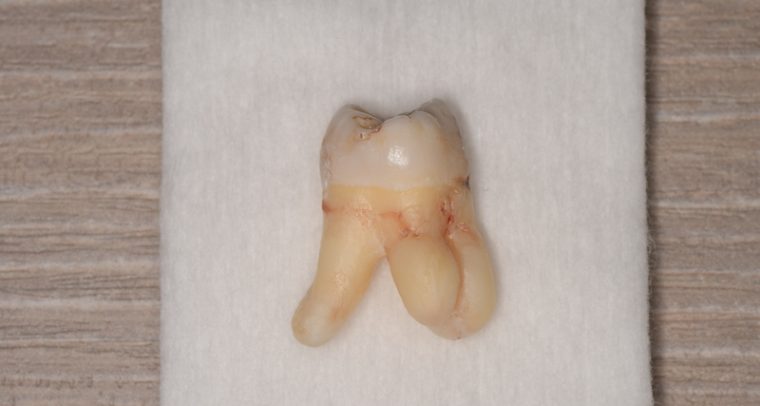

CASE 1

| 年齢・性別 | 30代・女性 |

| 主訴 | 左右に分けて親知らずを抜きたい、できれば痛くなく抜きたい |

| 親知らずのはえ方 | 完全に出ていてまっすぐはえている |

| 抜歯期間 | 15分 |

| 抜歯費用 | 約2,000円(保険内) |

| 抜歯内容 |

何度か虫歯になり痛みはないが早めに抜きたい。 完全に頭が出ているため歯ぐきを切ったり骨を削らずに抜歯しました。 根の形も単純なため抜歯自体は5分もかからず上下ともに終わりました。 術後痛みや腫れも出ていません。 抜歯後は感染をしやすいため必ず抗生物質を飲み切ってください。 |